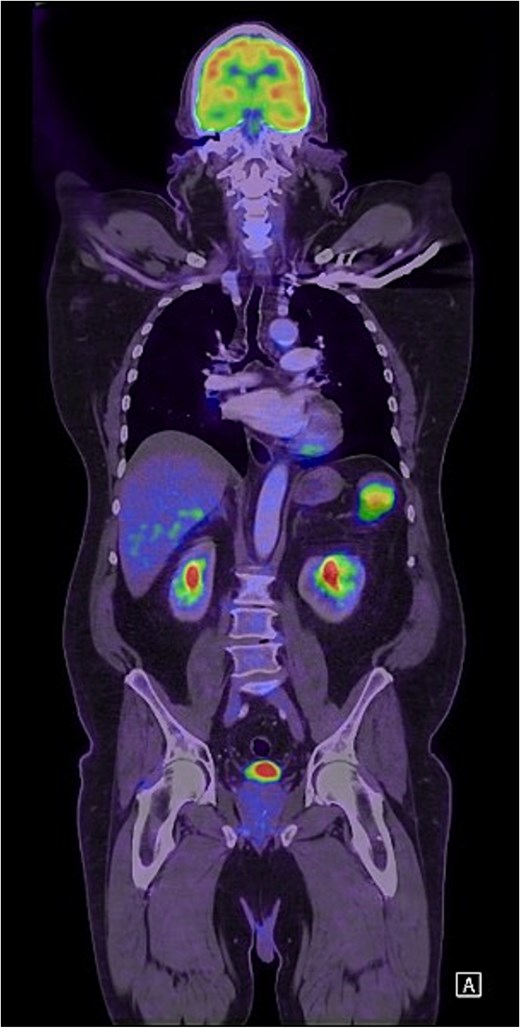

Unfortunately, 6 months later he was diagnosed with locally advanced squamous cell carcinoma of the face and was subsequently commenced on immunotherapy. As part of the work-up, he was re-staged with a positron emission tomography (PET) scan which found an isolated PET-avid soft tissue lesion in the LUQ measuring 51 × 37 mm in size (Fig. 3) for which he was clinically asymptomatic. Following multidisciplinary discussion, he underwent a laparoscopic soft-tissue resection with intraoperative findings of a mobile, soft tissue lesion located in the LUQ. Histology demonstrated foreign body granulomatous inflammation to cholesterol clefts in keeping with a CG. He had an uneventful postoperative recovery and remained asymptomatic on review in the surgical outpatient clinic.

Coronal FDG PET scan of the head, neck, chest, and abdomen demonstrating a PET-avid LUQ lesion.

Similarly, CGs are rare benign lesions with only limited case-based literature published to date. The pathogenesis is thought to be due to a breakdown of blood products secondary to either inflammation or trauma, leading to the production of cholesterol crystals that causes a granulomatous reaction [6, 12, 13]. In this case, bleeding or inflammation either from the primary IPT or secondary to the splenectomy is hypothesized to be the likely aetiology. Previous case reports have found CGs to be FDG-PET avid, representing a significant diagnostic pitfall to overcome with concomitant or previous malignancy and as a result, have often required upfront surgical management to accurately differentiate using histopathology [7, 13–15].